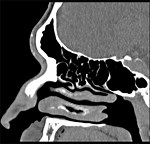

- Sinusite

Operation - Sinaus

Operation - Endscopy Nose Free

Stock Video - Endoscopic Sinus

Surgery Video - Nose Surgery